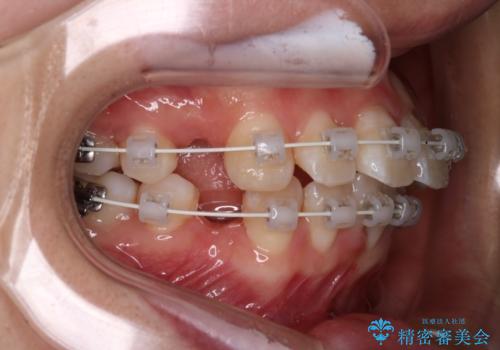

- 矯正装置

- 審美装置

- 治療計画

- 前歯のがたつきと口元を気にされて来院されました。

上下4番目の歯を抜歯してがたつきを改善しながら口元を下げる治療計画を立てました。